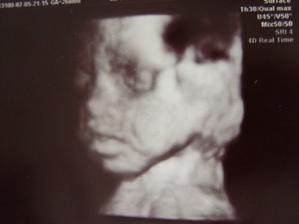

31.08.07 12:18 sa nám narodilo to najkrajšie dievčatko na svete Sofia,narástla nám 51 cm a vážila 3150 g.